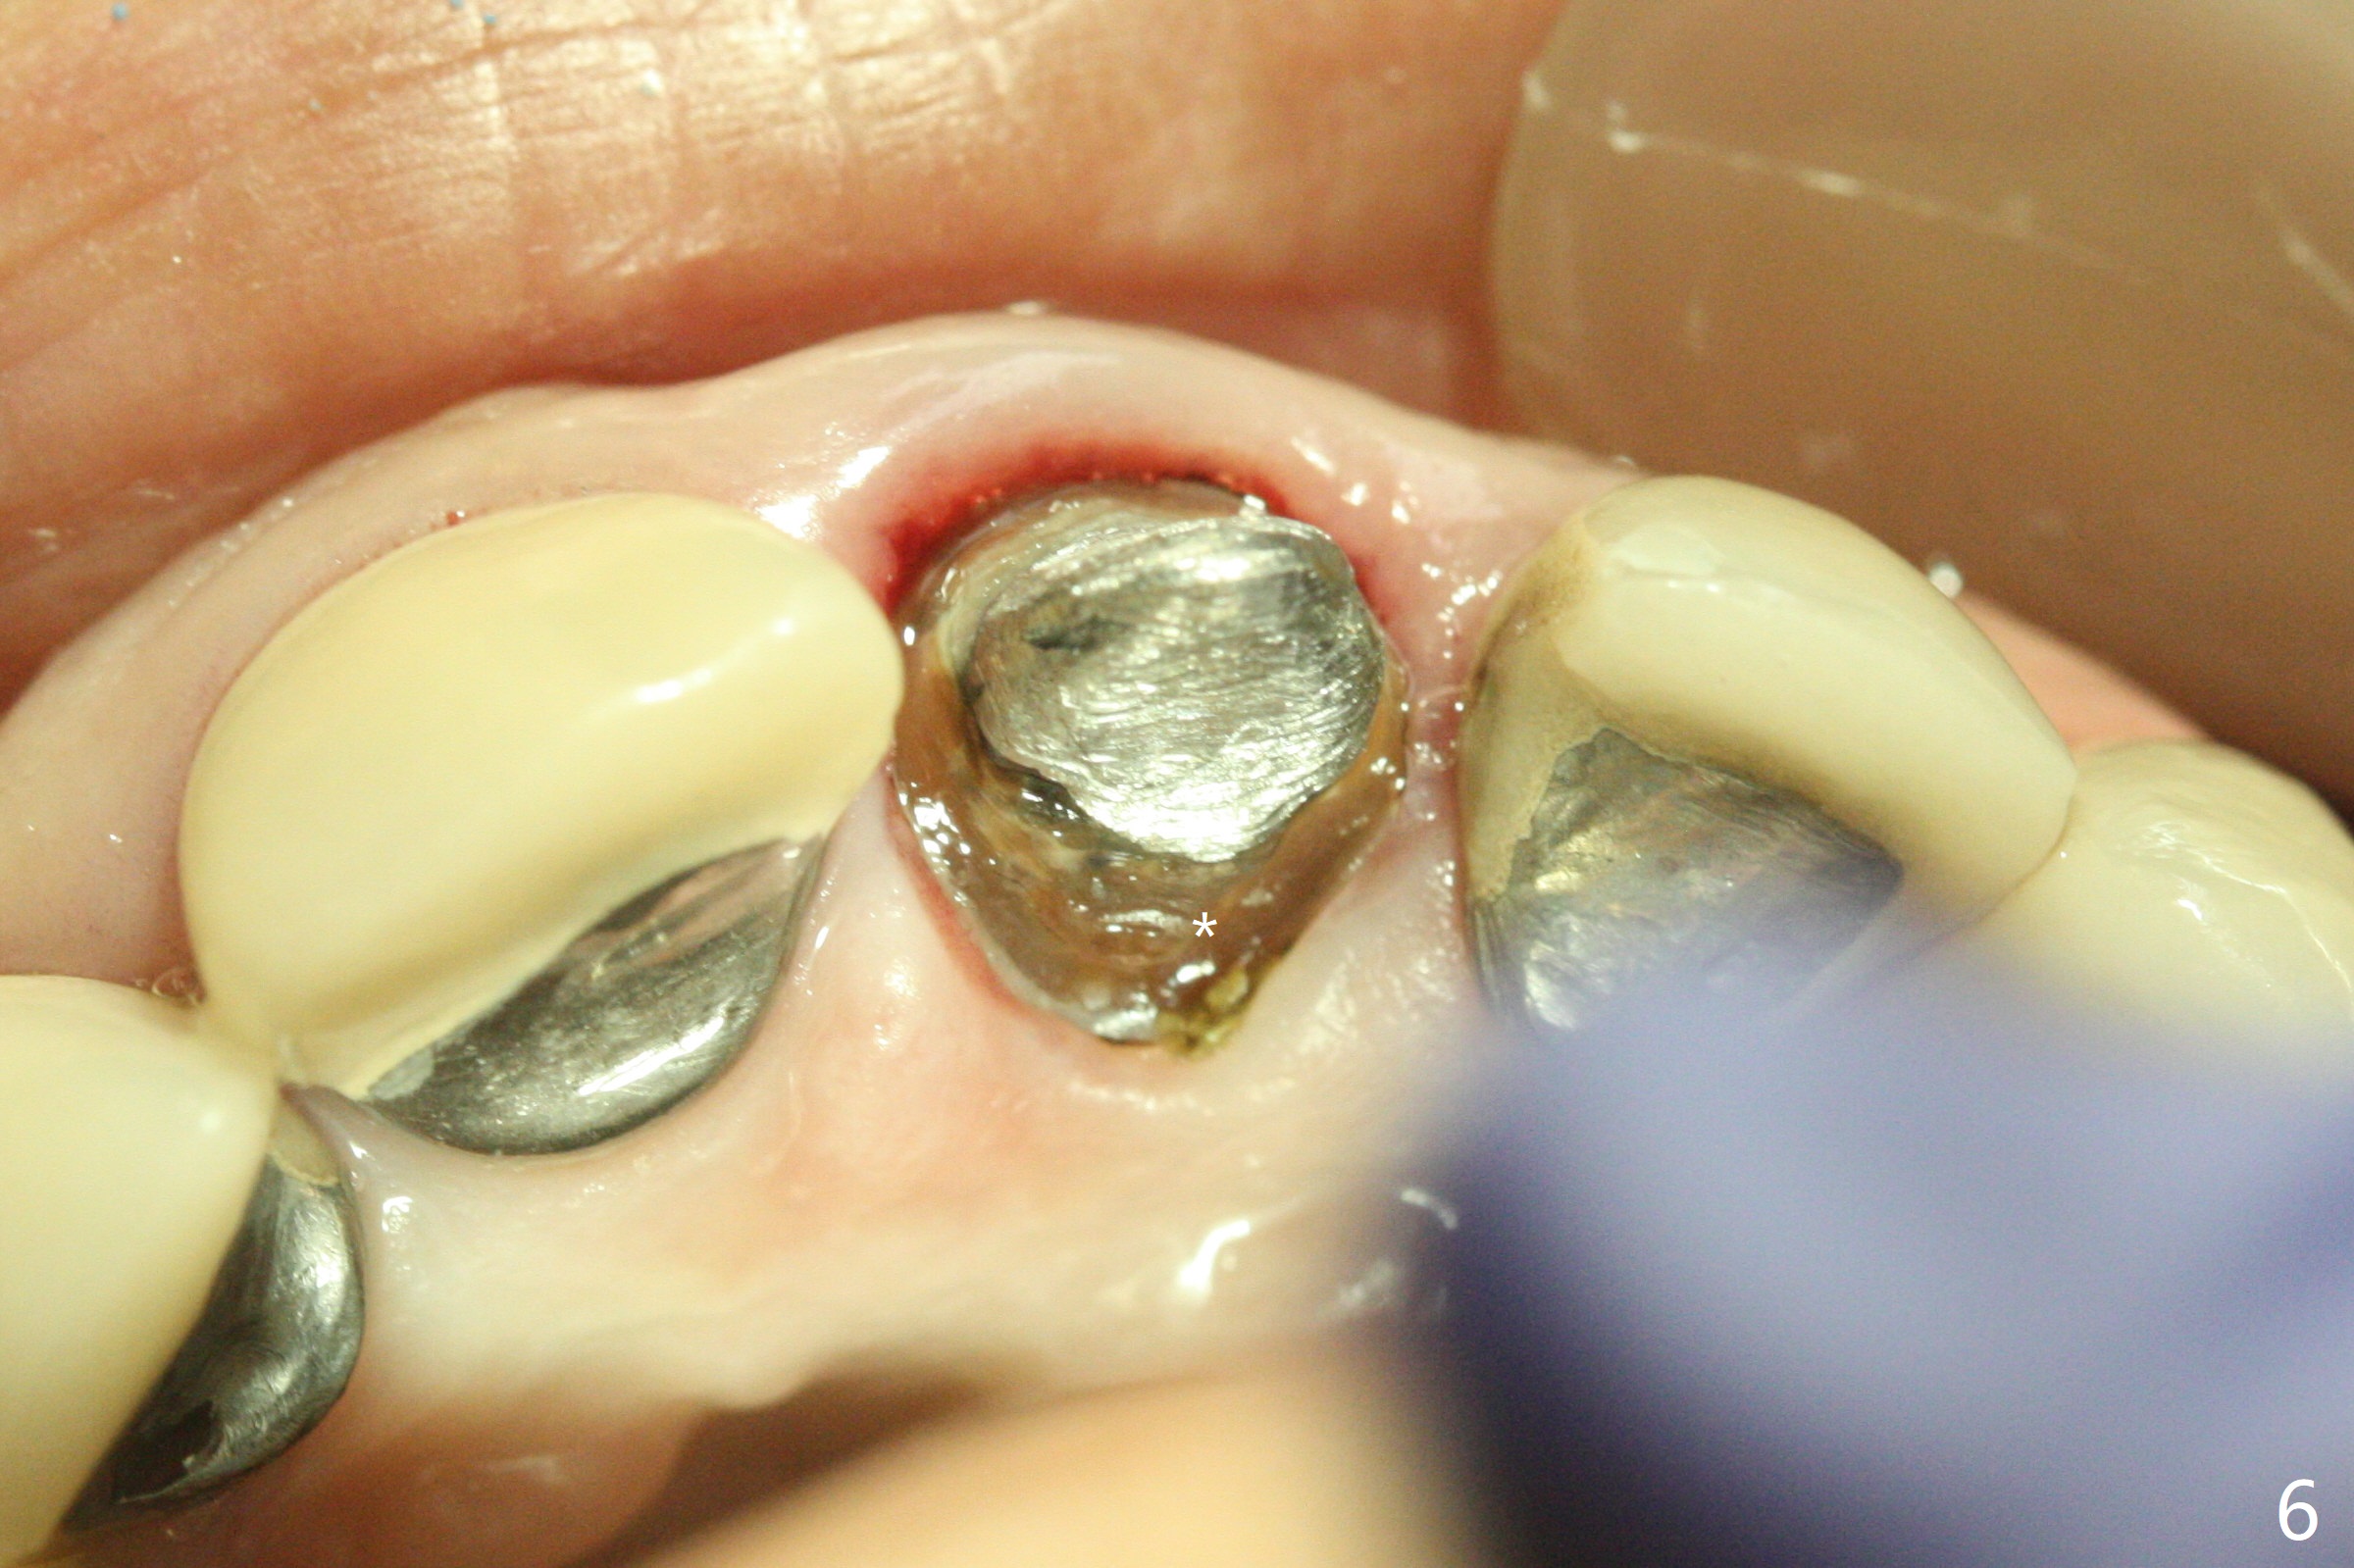

A 51-year-old woman with poor dentition has history repeated dislodged crown and post at #9. Finally the post fracture (Fig.1). After discussion of treatment options, she chooses to save the tooth. Treatment plan is to remove post, possible RCT retreatment, redo post and crown. The post remains stable following lengthy use of Piezo scaler (Fig.2). It appears that Piezo is quite aggressive, removing the tooth structure and the metal. Finally the coronal portion of the post is removed for cast post (Fig.3). There is approximately 2 mm for ferrule effect (Fig.4). The cast post is cemented with RelyX Ultimate and prepared for crown (Fig.5-7).